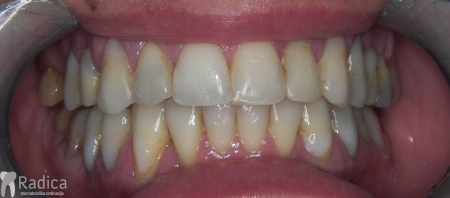

U sljedećem primjeru prikazan je pacijent s kompresijom koji je već bio u ortodontskoj terapiji. Za rješavanje kompresije donje čeljusti izvađen je sjekutić. Nkon terapije je došlo i do smanjenja recesija na očnjacima jer smo pomakli zubni korijen u bolji položaj.